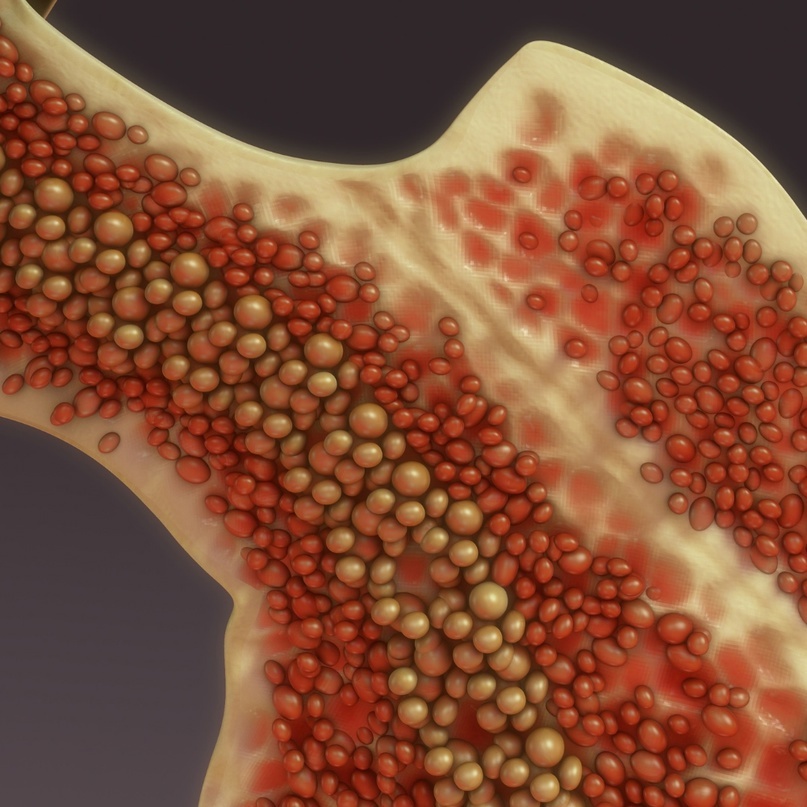

Дело в том, что костный мозг крупных костей, содержит жировую ткань. Зачем она там нужна и почему замещает собой ткань кроветворную (к 25 годам соотношение кроветворной ткани к жировой становится 4060% в пользу последней) – «сие тайна великая есть». Последняя и самая правдоподобная гипотеза – выполняет питательную функцию, для кости (кость сама по себе живая ткань и постоянно обновляется) и красного костного мозга. Именно в нём происходит формирование кровяных телец из стволовых клеток. При переломе, по этой гипотезе, происходит выброс жиров из разрушенных адипоцитов (жировых клеток). Жиры, попадая в кровоток, формируют глобулы и начинают путешествие по организму. Простое и элегантное объяснение. И действительно, свободные жиры в кровотоке неподалёку от перелома находят практически в 95% случаев, а значит дело закрыто?